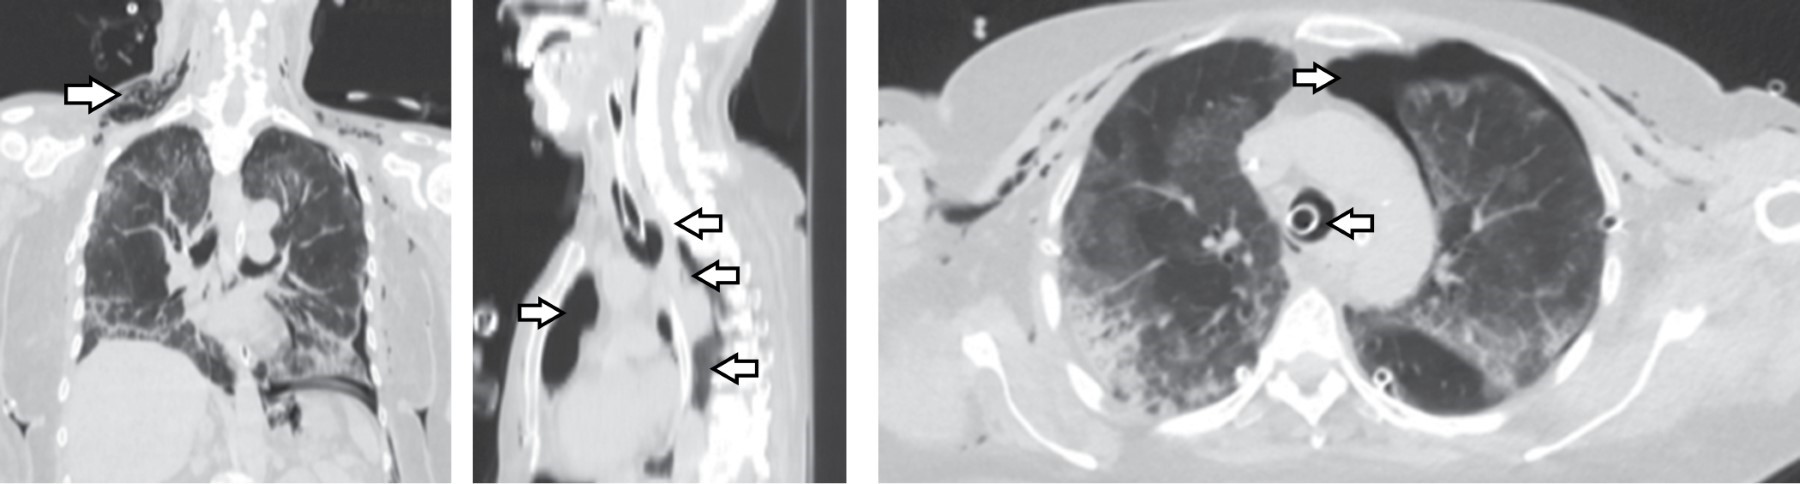

Femenino de 69 años. Ingresa a la Unidad de Terapia Intensiva (UTI) con diagnóstico de neumonía COVID-19, SDRA severo por Berlín con PaO2/FiO2 80 mmHg, pulsioximetría 92%, en ventilación mecánica invasiva (VMI) presión control 17 cmH2O, FiO2 60%, PEEP 12 cmH2O y frecuencia respiratoria 21/minuto. Al día 12 de VMI se realiza TP en la UTI con técnica de Ciaglia Blue Rhino.1 Se realiza incisión transversal de 2 cm a nivel del segundo anillo traqueal y punción entre el segundo y tercer anillo traqueal. A la aspiración se obtiene líquido citrino, por lo que se retira aguja y en una segunda punción se logra acceso efectivo. Se introduce cánula de traqueostomía de 8.5 mm y es conectada a la VMI; al momento presenta broncoespasmo tratado con broncodilatador y se realiza cambio de dispositivo a bolsa válvula mascarilla con reservorio; presenta resistencia a la ventilación con evidencia de enfisema subcutáneo masivo en tórax e hipoxemia por neumotórax a tensión bilateral; evoluciona a bradicardia y finalmente asistolia, se inician maniobras de reanimación, se realiza descompresión bilateral con aguja Punzocat no. 14, se asegura vía aérea con cánula orotraqueal de 8.5 mm al primer intento. Se logra retorno a la circulación espontánea con taquicardia sinusal e hipotensión, se colocan sondas endopleurales bilaterales y se procede a realizar fasciotomías pectorales para drenaje de enfisema subcutáneo; se observa en cámara de succión de Pleur-Evac® fuga aérea bilateral. Se recupera estabilidad hemodinámica a las 4 horas del evento y se realiza tomografía de tórax (Figura 1). La broncoscopia muestra laceración posterior de la tráquea (Figura 2). Por endoscopia se descarta lesión esofágica. El tratamiento inicial es conservador mediante ferulización traqueal durante 15 días. La broncoscopia de control muestra limitación de la perforación y tejido epitelizado; se decide cierre de lesión traqueal con parche de músculo esternohioideo izquierdo, se verifica aerostasia sin observar fuga (Figura 3). Se realiza traqueostomía a nivel de segundo y tercer anillo traqueal, y se coloca cánula de 7 mm Bivona® (Smiths Medical, Minnesota, EEUU), la rama distal queda pasando la perforación, se verifica aerostasia y hemostasia, se coloca drenaje Jackson Pratt® 10 mm (Bard, Covington GA USA) a lecho quirúrgico, con evolución radiográfica que demuestra expansión pulmonar, sin enfisema subcutáneo ni neumomediastino (Figura 4). Al quinto día del procedimiento quirúrgico cursó con broncoespasmo severo y obstrucción traqueal, presenta parada cardiaca sin lograr retorno espontáneo de la circulación.

Figura 1